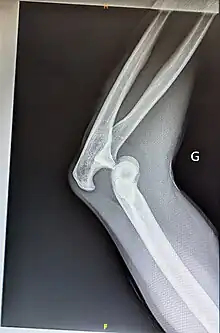

Luxation postérieure du coude gauche sans fracture associée

Luxation du coude

La luxation traumatique du coude est une lésion traumatique non rare, venant en second, derrière la luxation d'épaule.

Elle est habituellement réduite sans retard chez de grands enfants, adolescents ou adultes jeunes.

Une lésion traumatique survenant chez un petit enfant ou un adulte plus âgé est plus vraisemblablement associée à une fracture.

Seule est évoquée, la luxation pure ou seulement associée à un petit fragment osseux périarticulaire.